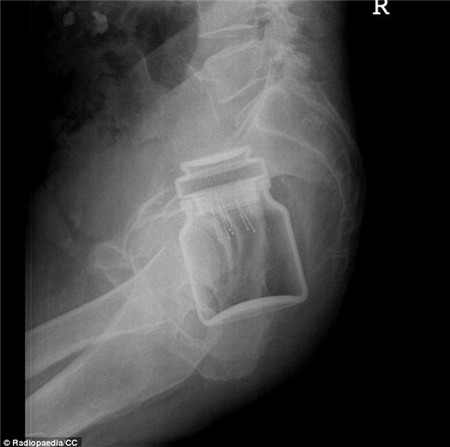

Trong

khi đó, một bệnh nhân khác thậm chí còn có một hộp café của một hãng

nổi tiếng trong người. Hộp café này vẫn còn nguyên nắp cao su.